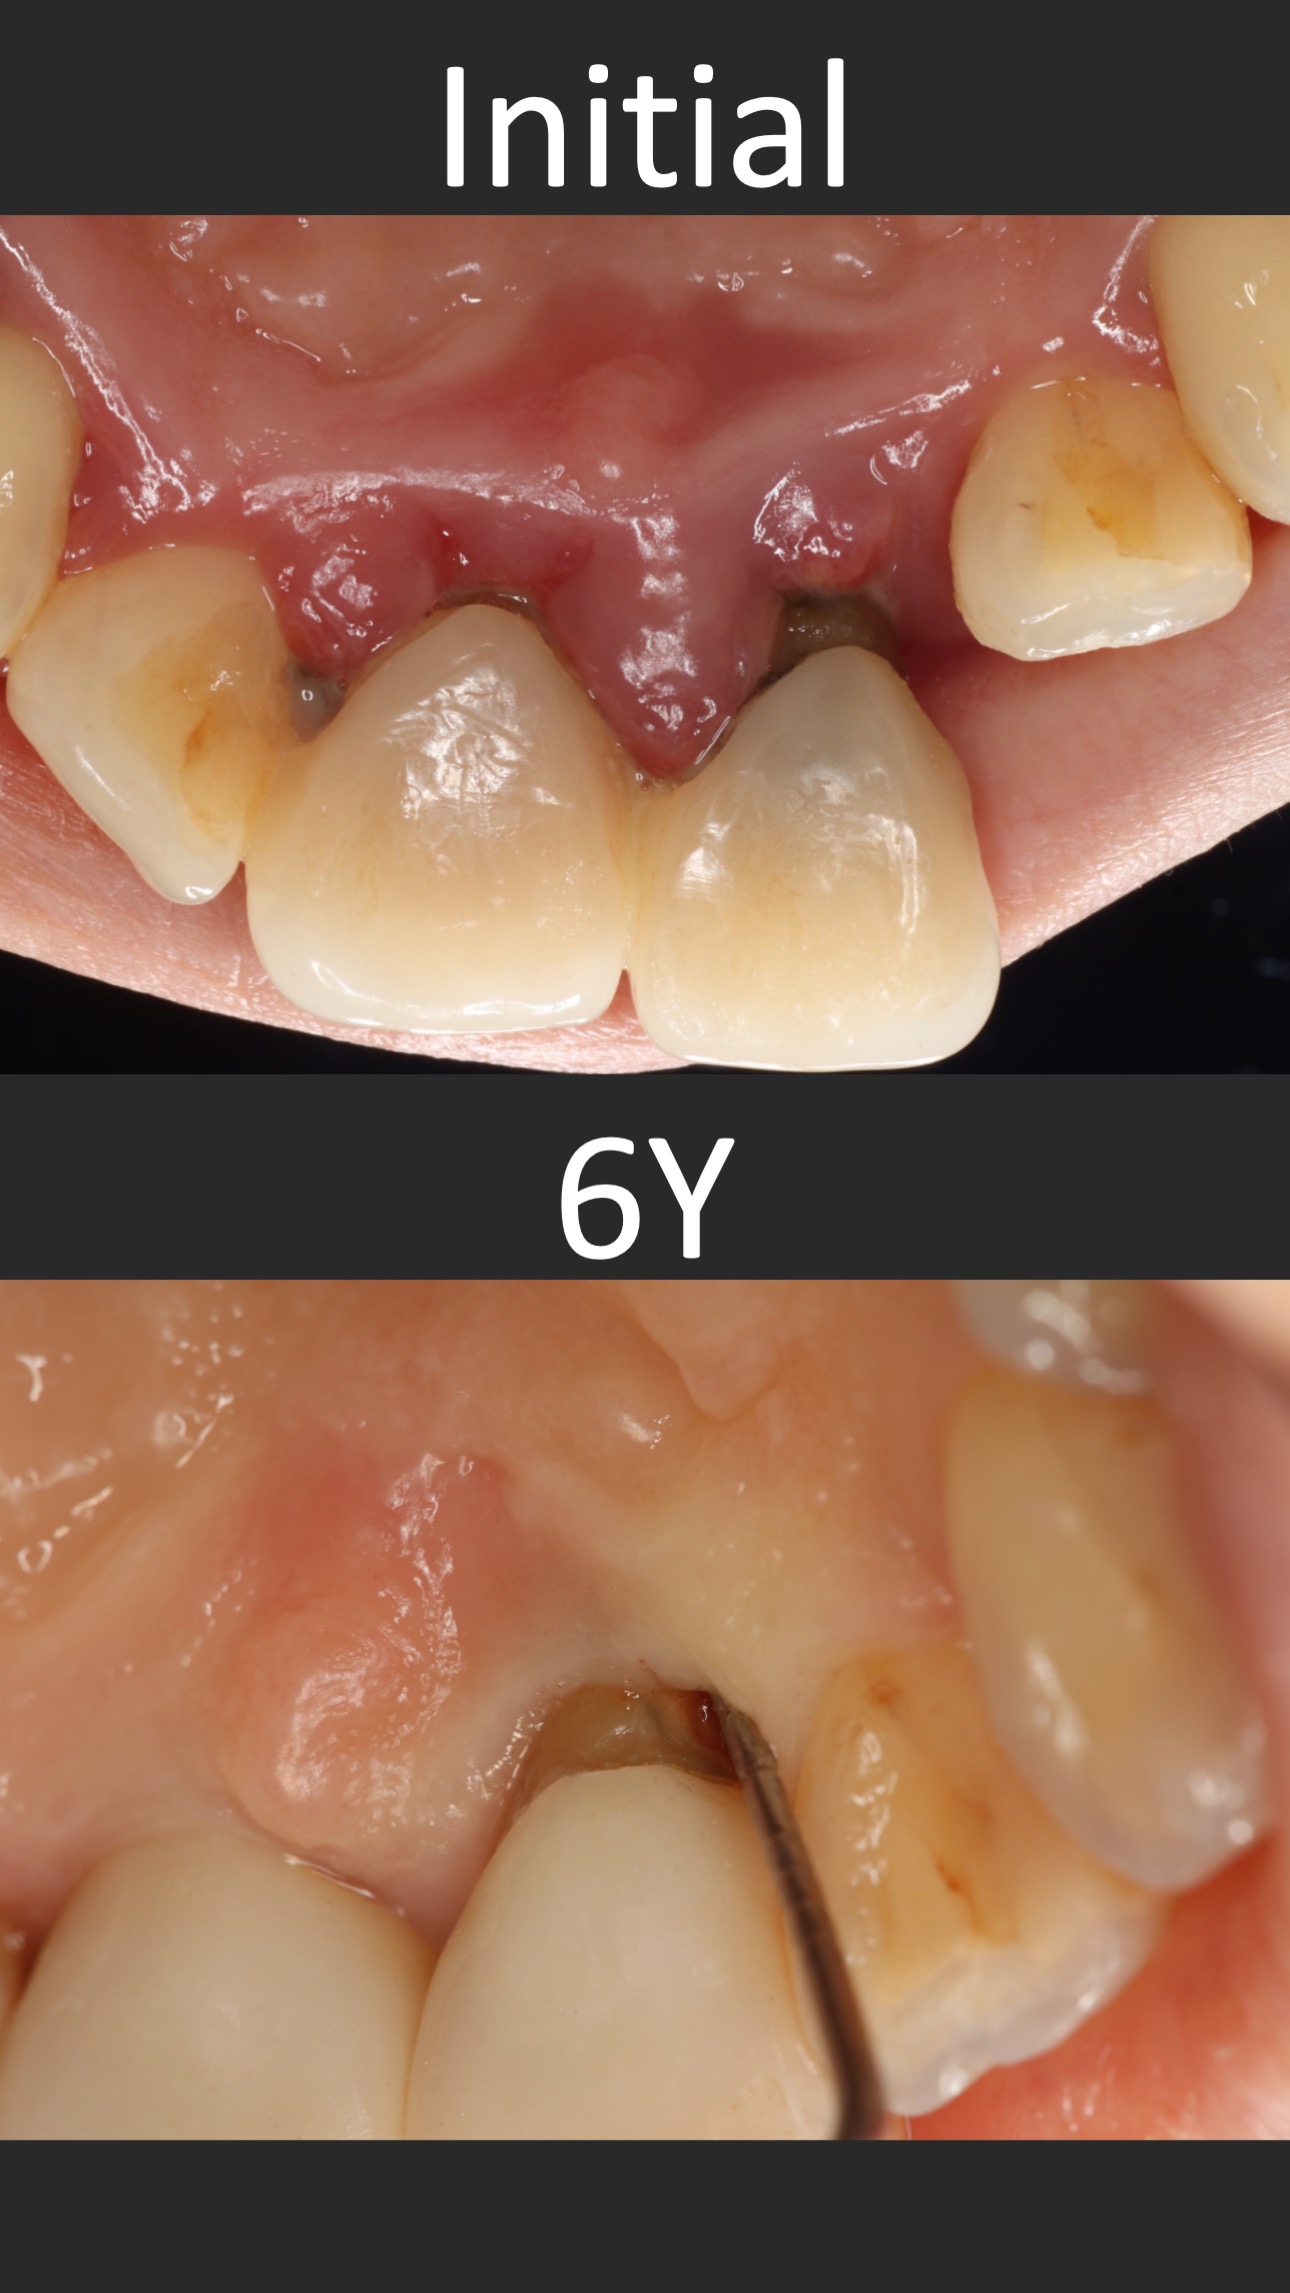

這個案例,最早沒把握能救回來,但是做完非手術治療,發現恢復非常好。

於是大膽地請矯正與假牙專科醫師一起幫忙完成。其實病人本身也同意,若途中狀況不好,還是得拔除。我知道這種案例,其實對其他專科來說,可能是有壓力的,不容易處理,也是難症。

好佳在,兩位神隊友都完成了,非常感謝合作專科的信任,還有,病患六年來維持得非常好,目前囊袋正常、零出血、零發炎。

回頭看,一開始就拔掉牙齒,改走其他路線,或許也可以,每位醫師選擇的或許不一樣,並沒有標準答案。

但是,能幫病患留下自己的牙齒,真的是很開心的一件事~~